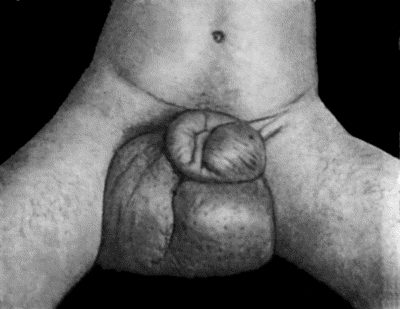

| 98. | Elephantiasis of Penis and Scrotum | 388 |